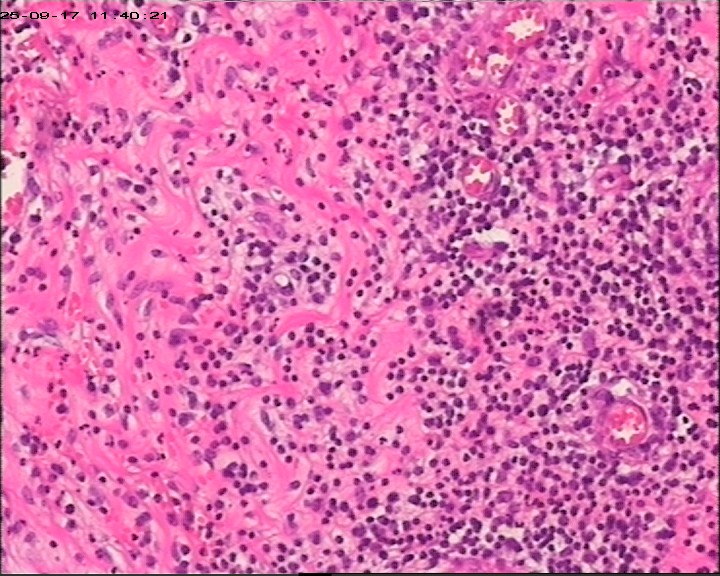

臀部组织,请帮忙看看,谢谢

性别

男

年龄

20岁

临床诊断

一般病史

藏毛窦或囊肿切开术

标本名称

臀部

灰白灰黄碎组织一堆,大小为6.5*4*1cm。

描述诊断炎性病变